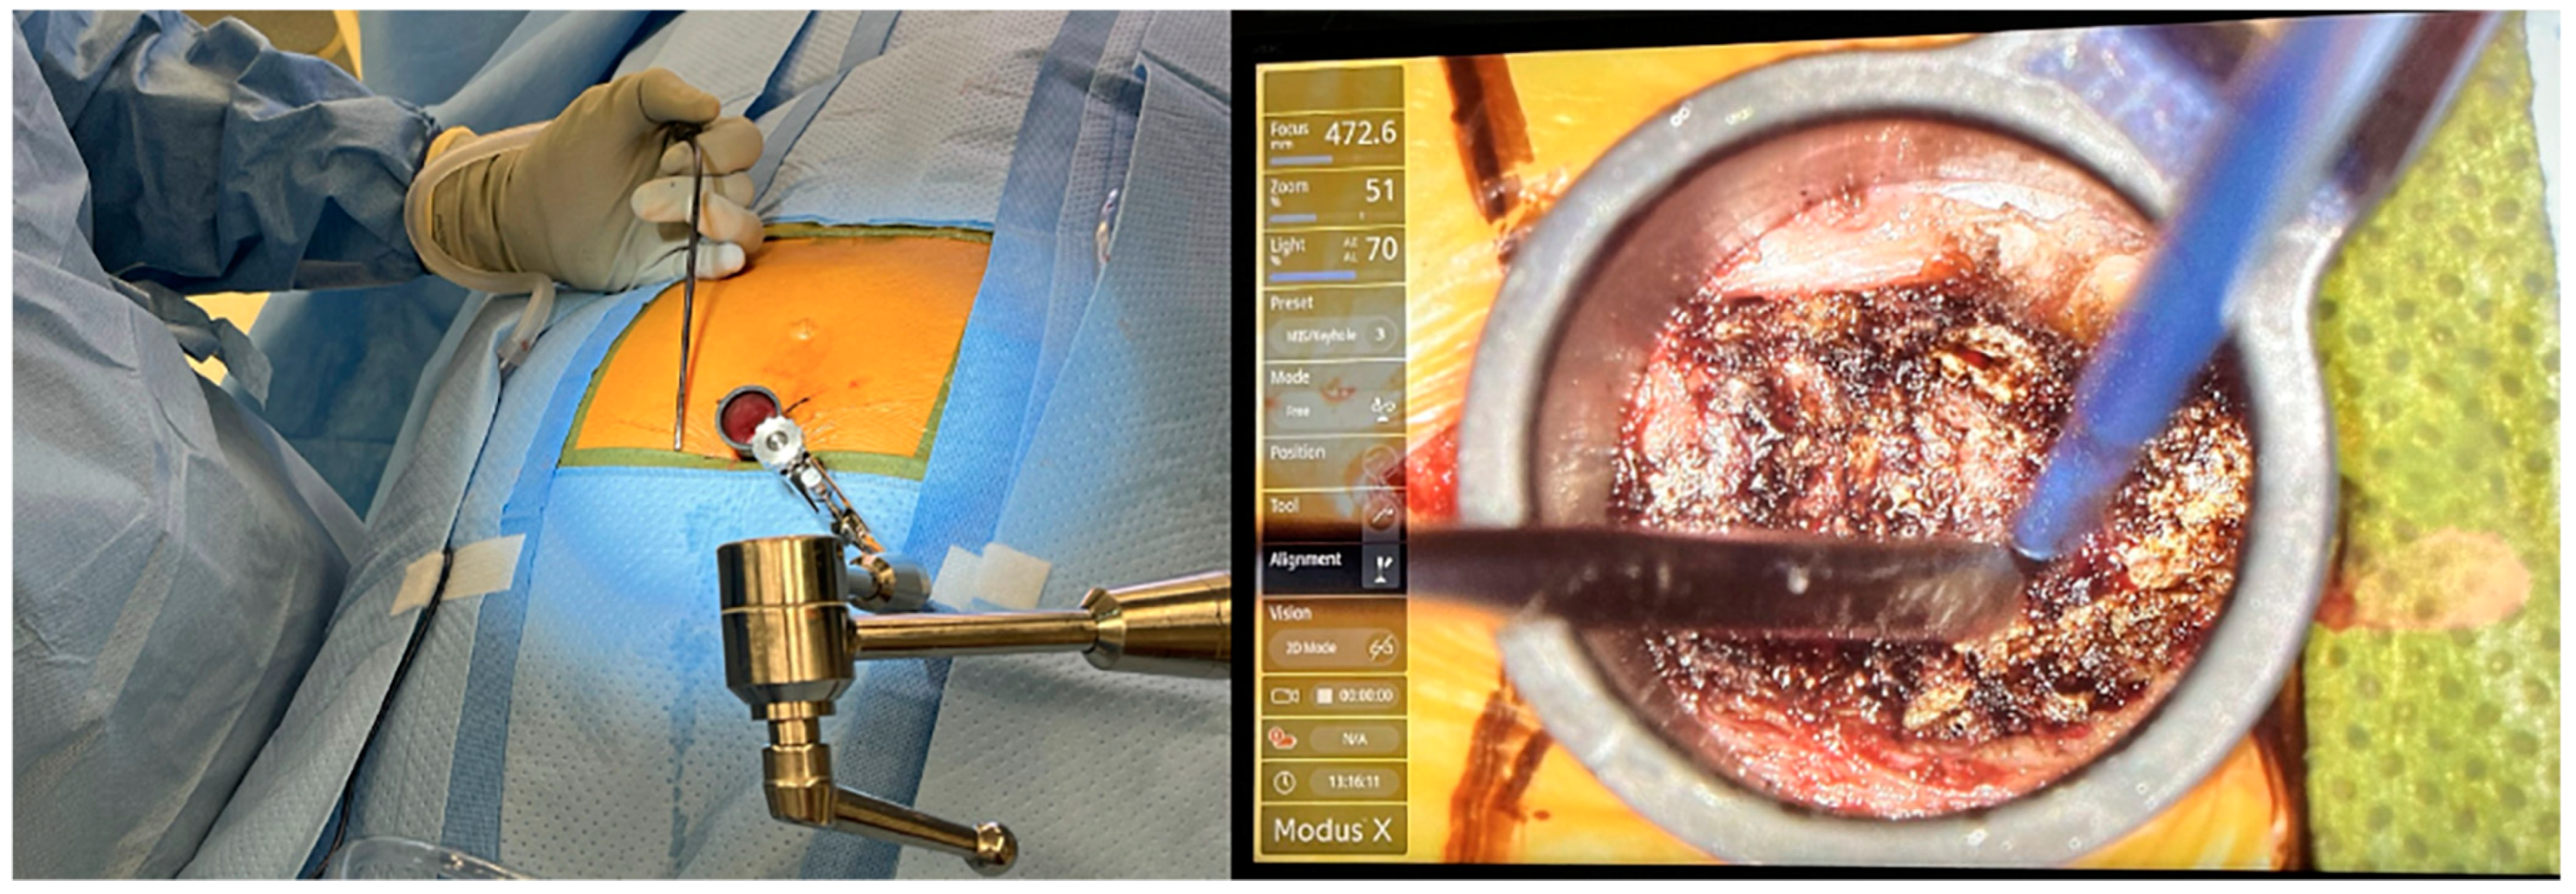

During an endoscopic coccygectomy, small incisions are made, and endoscopic instruments are inserted to visualize and operate on the coccyx (Figure 1 and Figure 2). This approach allows for precise removal of the affected coccyx segment while minimizing damage to surrounding tissues. The endoscopic method provides surgeons with better visibility, increased accuracy, and the ability to perform the surgery with less invasive maneuvers [24].

Figure 2. Minimally Invasive Coccygectomy Performed through METRx tube. The extent of exposure achieved during endoscopic approach can be visualized, as indicated by surgical instruments.